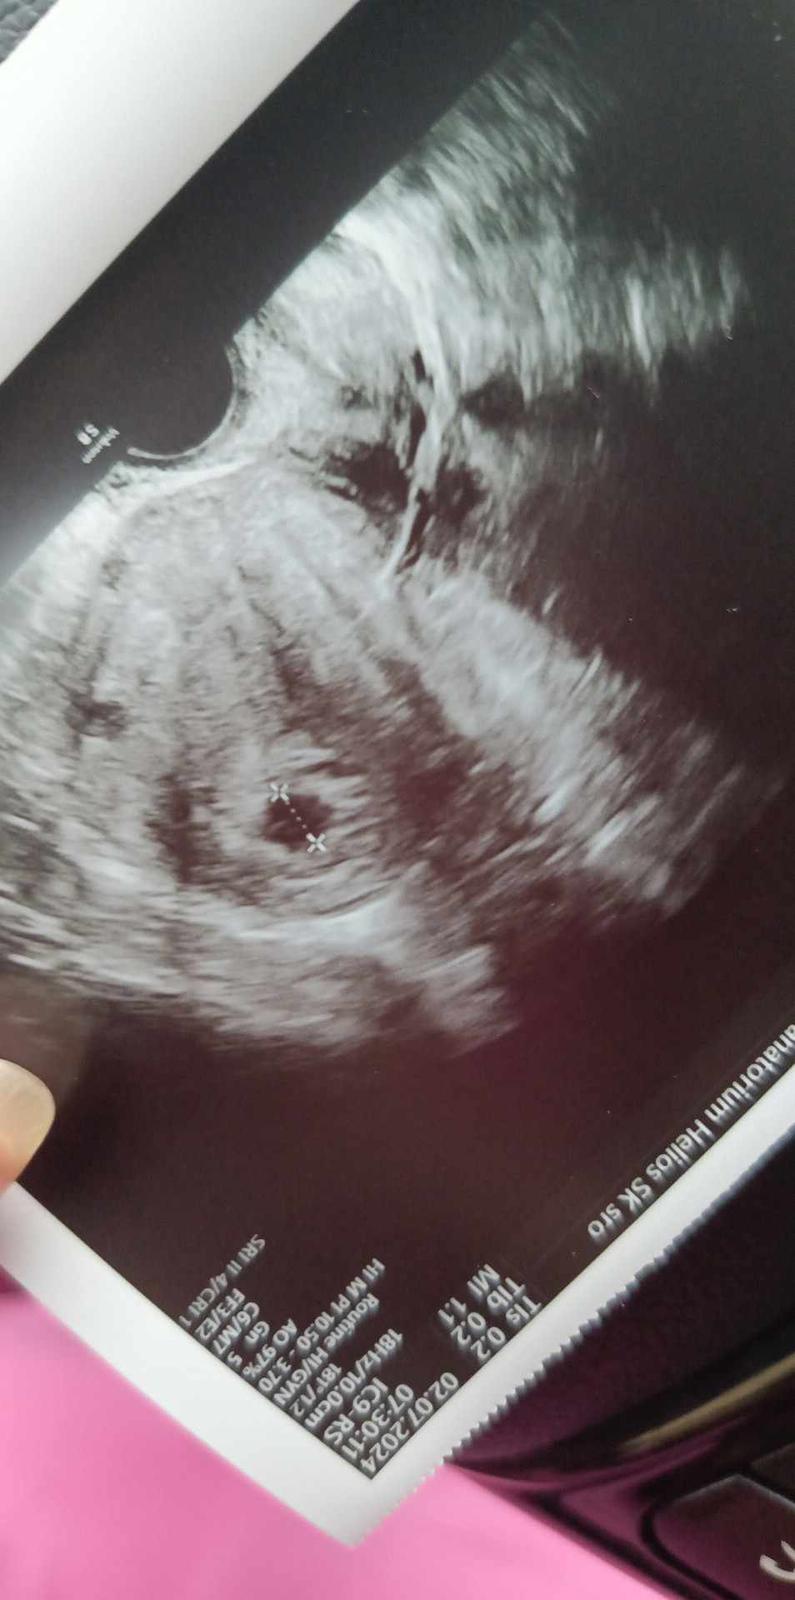

@enuska62856 .. vacok je na správnom mieste .. akurát mi povedal že tam mám všetko čo sa dá mať ... Nie v dobrom slova zmysle .. tak E sa mám šetrite a udržať to .. ešte keby som vedela ako .. mám tam myomy a ešte niečo ale ozaj že si nepamätám čo .. neviete mi dať nejaké napovedy čo by som tam ešte mohla mať ? Bol to nejaký dlhý názov